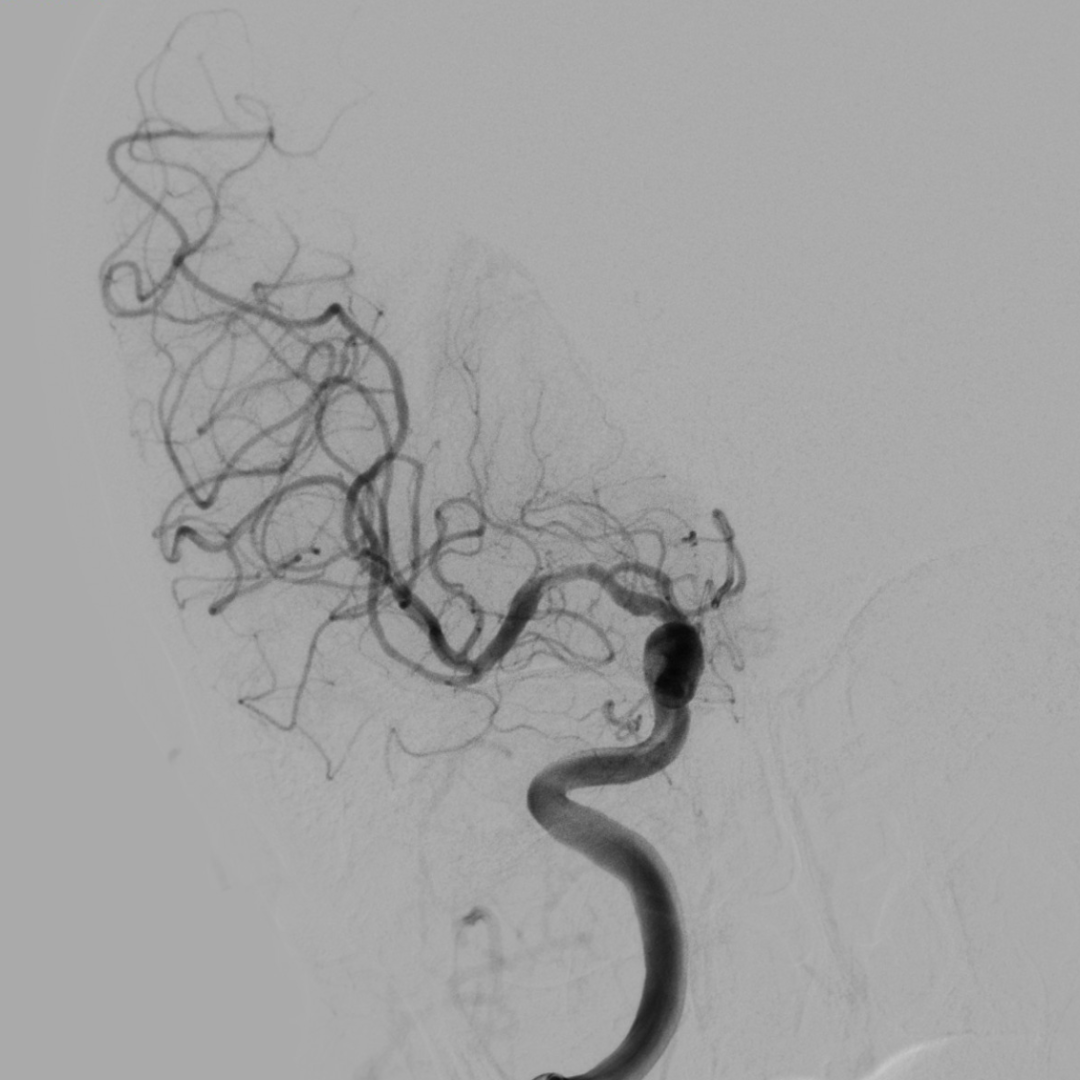

扩张后造影见血流改善,支架内未见明显血栓影。

观察10分钟回收支架后,继续观察15分钟提示血流良好。